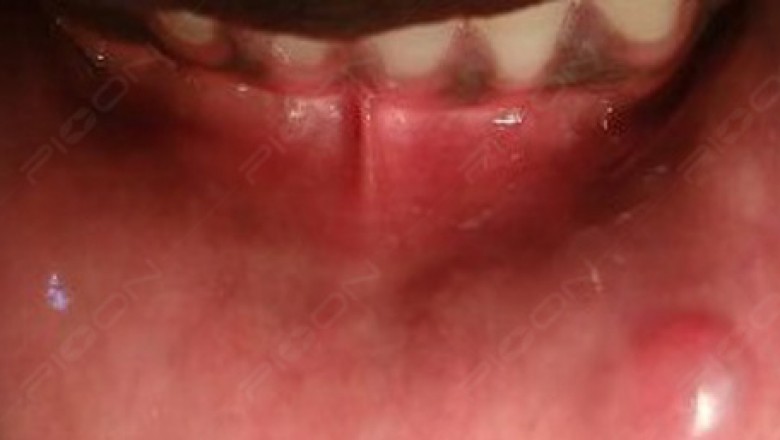

Clinical Features- Fibromas are often found on the interior of the cheek, lips, or lateral borders of the tongue and result from tissue being trapped between the maxillary and mandibular teeth when occluding. An oral fibroma presents as a firm smooth lump and is usually similar in color to the surrounding soft tissue, although it may be paler due to less vascularity and increased connective tissue within it. A fibroma also may present darker if trauma has led to bleeding inside of it and may have an ulcerated surface related to recent trauma. Fibromas have a dome-shaped geometry but may be pedunculated (polyp-like with a short stalk-like base).

With the advent of lasers for soft-tissue surgeries, various types of laser devices have been used successfully for oral fibroma removal. Laser selection is practitioner dependent. PIOON Laser offers different wavelengths like 450nm/810nm or 980nm. The most preferred among them is 450nm wavelength. After informed consent, the lesion was infiltrated with local anesthesia, the protective eye wear were worn and then the lesion was excised using 450nm in noncontact mode with surgical tip (400µm) making sure to remove the stalk attaching the lesion. After the procedure, postoperative instructions were given and analgesic was prescribed on as and when basis.